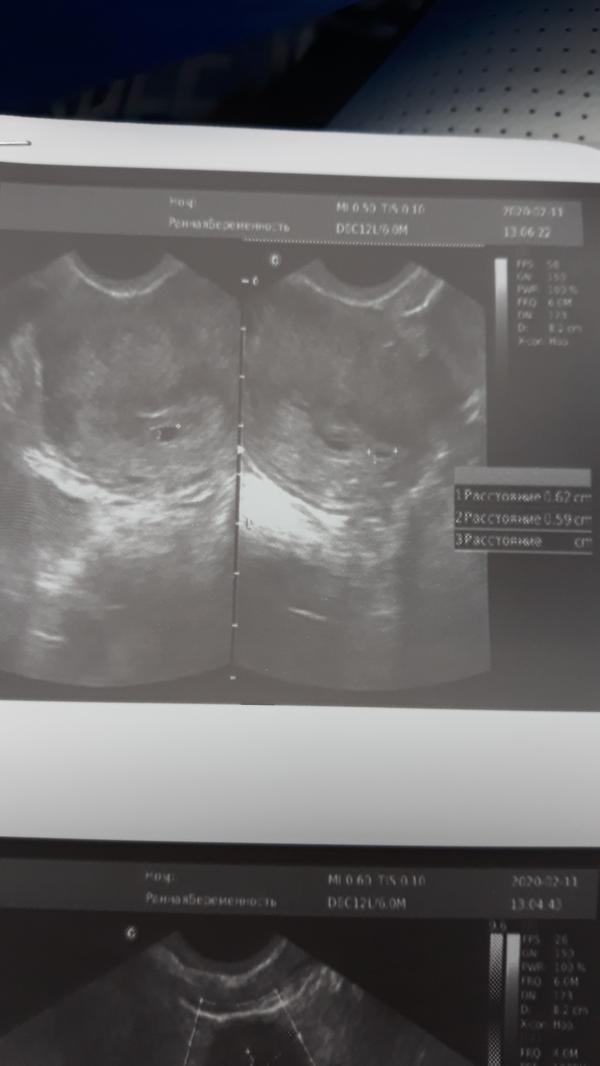

Все привет))) я тут новенькая, есть вопрос по беременности, может у кого так было? Последние М былы 06.01, до задержки сделала тест, положительный, 04.02 вечером началась мазьня,к утру все прекратилось, вызвала скорую, сделали узи, в матке ПЯ еще не было, сдала кровь на ХЧГ 488, через два дня 1022, еще через три дня Узи, угрозы нет, на вопрос а почему была кровь сказали возможно имплантанционное кровотечение, увидели 2 ПЯ))) Но, врач была не уверенна насчет второго, т.к еще маленькие, сказала ...